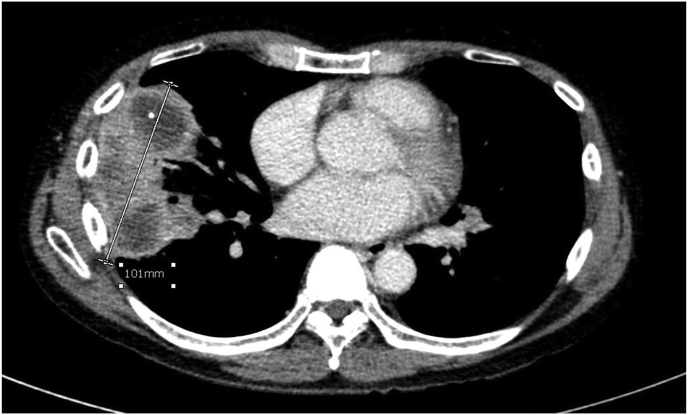

Chest radiography showed multiple pulmonary nodules in both lungs. A chest CT showed multiple lung masses with peripheral enhancements and perilesional ground glass opacities, the largest mass was 10.1 × 5.6 × 6.0 cm. Sub-centimeter mediastinal lymphadenopathy was noted (Fig. 1a). An abdominal CT showed 10.5-cm heterogenous enhancements of the spleen without space-occupying lesion. Liver and portal veins were unremarkable. Neither adenopathy nor ascites were seen.

Fig. 1a.

Chest CT showed the largest pulmonary mass at lateral segment of right middle lobe.